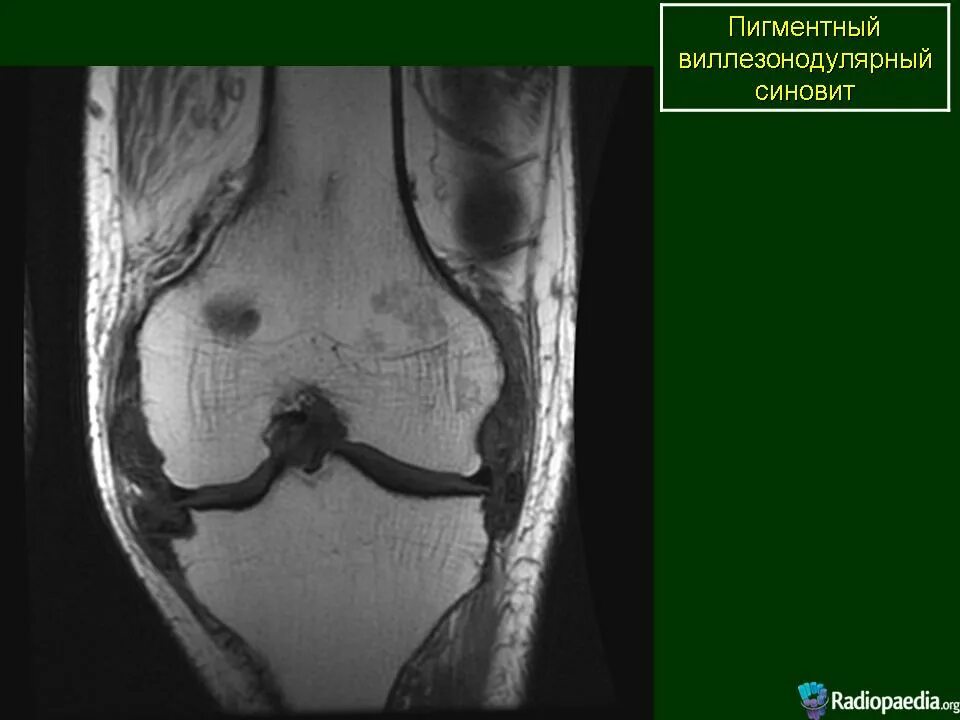

Пигментный виллонодулярный синовит